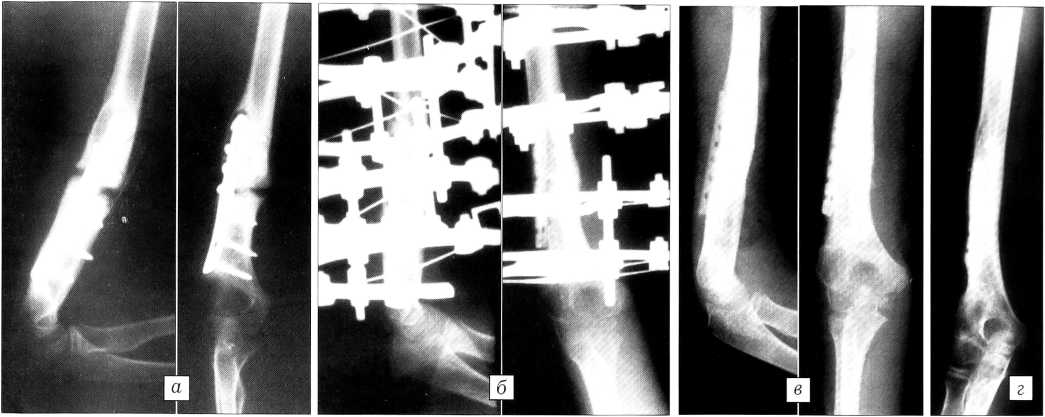

Больной Ш.,9 лет, в результате удара тяжелым предметом получил открытый перелом плечевой кости на границе средней и нижней трети. В первые дни после травмы был произведен остеосинтез штифтом Богданова. Через 4 мес консолидации отломков не наступило. Штифт был удален, выполнен остеосинтез пластиной. Через 10 мес после этой операции сформировался ложный сустав плечевой кости (см. рисунок, а).

Ребенок был госпитализирован в ЦИТО, где произведено удаление металлической пластины, выполнены экономная резекция ложного сустава и пристеночная костная пластика деминерализованным перфорированным костным имплантатом в сочетании с остеосинтезом в аппарате Илизарова (см. рисунок, б). Через 4 мес ложный сустав сросся и аппарат был демонтирован (см. рисунок, в). Через 13 мес отмечается резорбция имплантата, прорастание его тканью больного (см. рисунок, г). Функциональный результат оценен как отличный.

Рентгенограммы больного Ш.

а — при поступлении в ЦИТО: сформировавшийся посттравматический ложный сустав плечевой кости после лечения методом накостного остеосинтеза;

б — после резекции суставных поверхностей ложного сустава и выполнения костной пластики в сочетании с чрескостным остеосинтезом в аппарате Илизарова;

в — через 4 мес после операции: консолидация перелома;

г — через 13 мес после операции: картина перестройки поверхностно-деминерализованного костного имплантата.